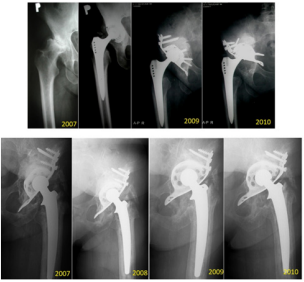

Finally, Peters et al. [5] had earlier noted poor long-term results for the BS plate in resolving pelvic discontinuity. The stability of the BS plate can be assessed by x-ray, and the imaging findings can help to predict its duration over the long-term. To this end, Gill et al. [6] showed plate instability as being indicated on x-ray by fracture of the proximal screws in the plate, together with proximal-migration of more than 5 mm, and with progression of radiolucent lines. Moreover, Van den Linde and Tonino [7] showed that fracture of the proximal screws without subsequent migration of the plate or change of inclination on x-ray does not equate to plate loosening. Our x-ray analyses agreed with these reported parameters (Figure 3). In addition, Gross et al. [8] showed that resorption of the bone grafts implanted into the pelvis upon re-implantation served as a marker of plate stability, as evidenced by x-ray imaging. This study was designed to Gross et al. [8].

Figure 3: Representative case of fracture located proximally in the BS plate but without loosening. The three x-ray images were taken over a 6-year period, as indicated. The fractured screws are indicated by yellow arrows.